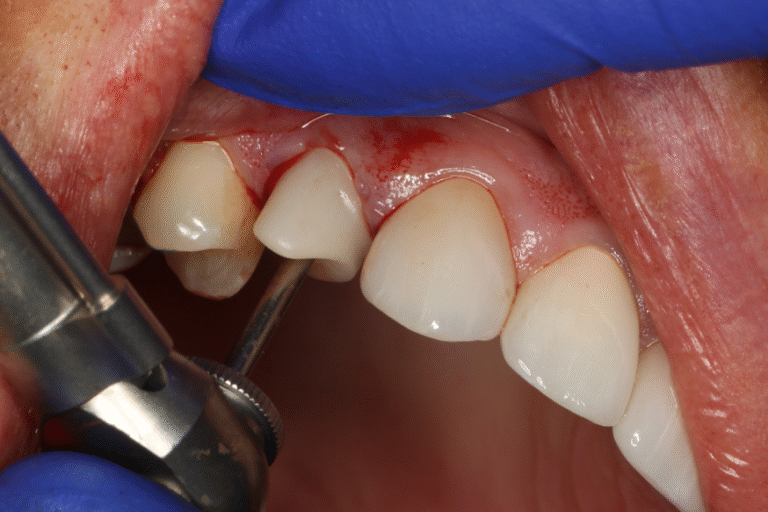

Apex Locator Guide

Due to a lack of adequate buccal bone, it is occasionally neccesary to perform Partial Extraction Therapy (PET) or the Socket Shield Technique.

These guides guide a 2mm drill to the apex of the tooth to be extracted, simplifying and speeding up the process.

Since the planning for the PET is done at the same time as the planning for the implant placement, we ensure that the socket shield will not interfere with the planned implant position.